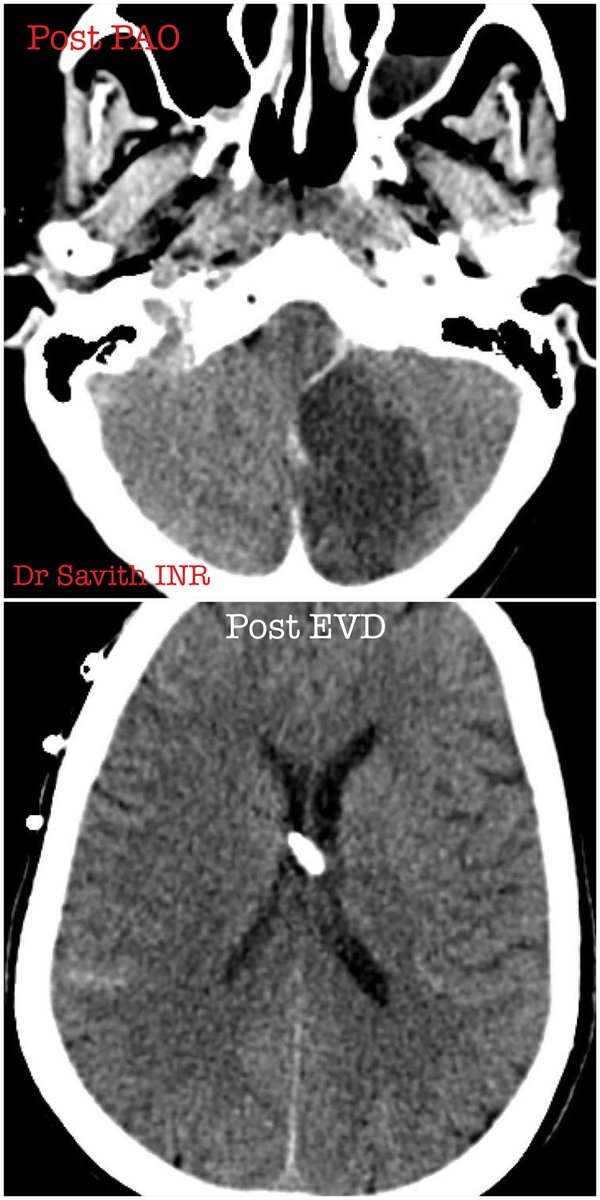

60 year old female with SAH and hydrocephalus from ruptured left PICA dissecting aneurysm. Partent artery occlusion done followed by EVD. Follow up CT showed left PICA territory infarct. Neurological stable. #aneurysm #neurointervention #coiling